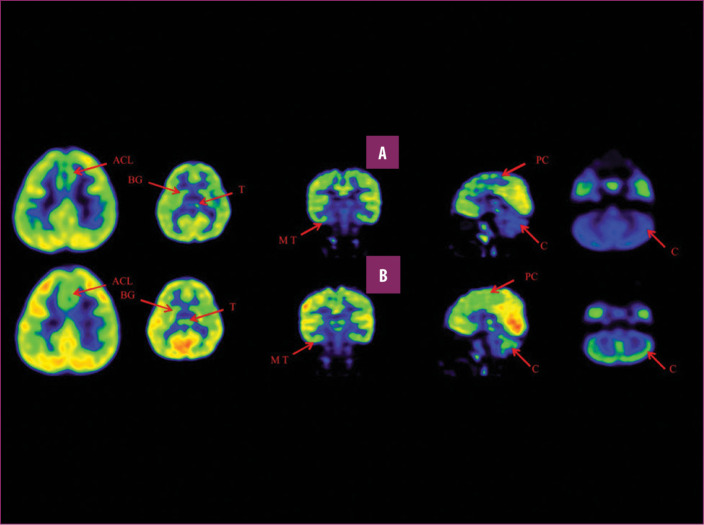

前扣帶回 (ACL)、頂葉皮層 (PC)、內(nèi)側(cè)顳葉皮層 (MT)、基底神經(jīng)節(jié) (BG)、丘腦 (T) 和小腦 (C)。B 行)第一次移植后6個月后PETCT腦部掃描的干預(yù)后圖像顯示標(biāo)記區(qū)域有所改善。藍(lán)色代表代謝減退區(qū)域。綠色代表正常的新陳代謝區(qū)域。圖A和B的比較顯示藍(lán)色區(qū)域顯著減少,綠色區(qū)域增加,這表明大腦的新陳代謝得到改善。

與之前的情況相比,他在矢狀面和額狀面上的體重變化有所改善;頭部、軀干和骨盆的排列也得到改善,雙側(cè)腿筋和小腿肌肉的緊繃感也有所減輕?;颊唛_始執(zhí)行雙手任務(wù)。在認(rèn)知方面,由于他定期上學(xué),他的注意力持續(xù)時間和久坐耐力也得到了改善。GMFM評分從60.67提高到67.75;GMFCS等級由Level3提升至Level2;和FIM評分從97分提高到99分。在比較第一次細(xì)胞治療之前和之后七個月期間進(jìn)行的腦部PETCT掃描結(jié)果時,前扣帶葉、頂葉皮層、內(nèi)側(cè)顳葉皮層、丘腦、基底神經(jīng)節(jié)和小腦(表格1)。